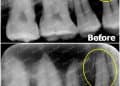

- 4.病理性變色方面

當牙齒出現包含蛀牙、牙面脫鈣、牙神經壞死或牙根痠軟等,「牙齒或牙根變黃」反而是牙齒的求救訊號。柏登牙齒健白團隊建議先請牙醫師做徹底的檢查與根本治療後,再尋求牙齒美白療程,才能真正達到牙齒暨「健康」又「美白」的終極目標。